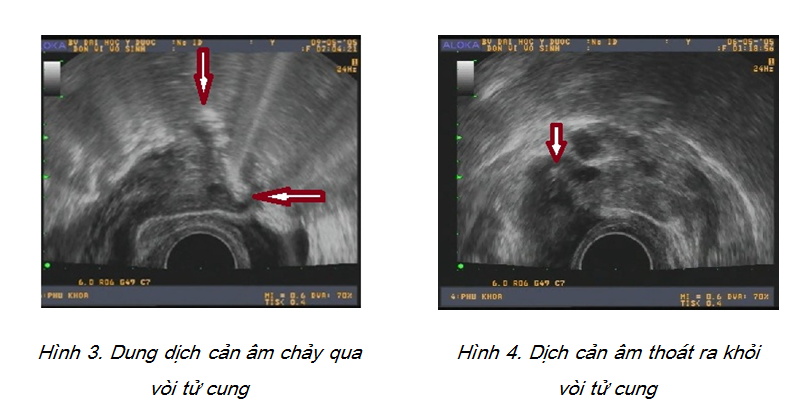

Sau khi bơm dịch muối sinh lý vào buồng tử cung, tiến hành bơm tiếp dung dịch nước khoáng có gaz đã được lọc và lắc kỹ. Bơm chậm 20-30ml dịch và quan sát dưới siêu âm qua đầu dò âm đạo. Hướng đầu dò từ buồng tử cung theo mặt phẳng ngang lần lượt về sừng tử cung mỗi bên và quan sát dòng chảy của dịch cản âm đi theo vòi tử cung ra hố chậu. Kết quả đánh giá sự thông vòi tử cung được chia thành ba nhóm: lưu thông tốt, giãn ứ dịch và tắc hoàn toàn.

Bơm dịch khoáng cản âm được tiến hành sau khi bơm nước muối sinh lý. Kết quả của chúng tôi ghi nhận tổng số các trường hợp có tắc, giãn ứ dịch một hoặc hai bên vòi tử cung là 28 trường hợp, chiếm tỉ lệ 21,1%. Đây là một tỉ lệ đáng lưu ý trong những trường hợp đang mong muốn có thai. Nguyên nhân vô sinh do vòi tử cung là một trong những nguyên nhân thường gặp nhất ở Việt Nam (Cao Ngọc Thành, 2011). Bằng phương pháp thăm dò rất đơn giản như HyCoSy, khả năng sàng lọc và phát hiện sớm bất thường sự thông của vòi tử cung đủ để hướng đến chẩn đoán nguyên nhân cho các trường hợp vô sinh.

Một số nghiên cứu trên thế giới có tỉ lệ bất thường vòi tử cung qua HyCoSy tương tự kết quả của chúng tôi: 21% (Ayida và cs., 1996), 26% (Lindborg và cs., 2009), hay 29,2% (Shahid và cs., 2005), thậm chí còn cao hơn, đến 31,2% (Volpi và cs., 1996) hay 40% (Bello, 2004). Bằng dung dịch nước khoáng có gaz, chúng tôi đã thu được hình ảnh khá rõ nét của dòng dịch chảy qua vòi tử cung và vào hố chậu. Tuy nhiên, trong một số trường hợp, tư thế vòi tử cung ngoằn ngoèo làm cho việc khảo sát dòng chảy khá khó khăn do mất liên tục. Trong hầu hết các trường hợp tắc vòi, khi không thấy dòng dịch chảy ra loa vòi, chúng tôi không thể xác định được vị trí cuối cùng của luồng dịch (tức vị trí tắc trên vòi tử cung).